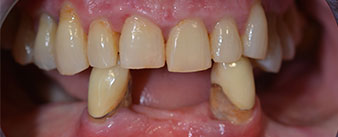

The 64-year-old patient presented with residual dentition of teeth 38, 33 and 43 and a clasp denture in the mandible (Fig. 1 and 2).

residual dentition

Fig. 1

Fig. 2

The necessary periodontal treatment and extraction in the maxilla was to be performed at a later point in time, as the patient is a teacher and was busy with school leaving exams at the time. She could neither eat nor speak properly, as the temporary prosthesis was very fragile, breaking regularly and under the slightest strain.